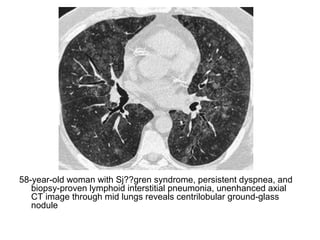

58-year-old woman with Sj??gren syndrome, persistent dyspnea, and

biopsy-proven lymphoid interstitial pneumonia, unenhanced axial

CT image through mid lungs reveals centrilobular ground-glass

nodule